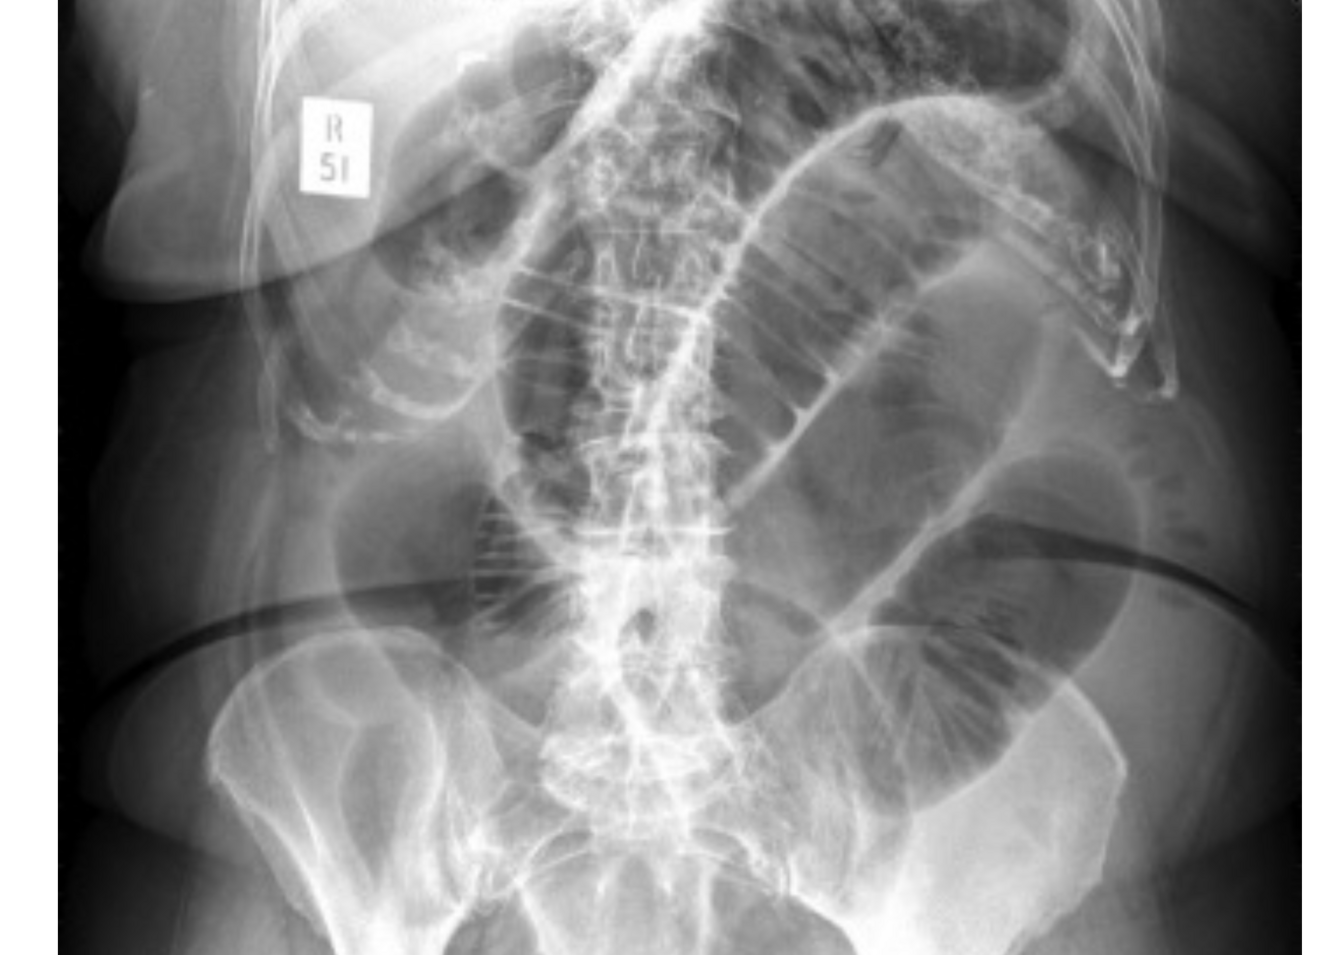

Q

A

SBO

further investigations for bowel obstruction